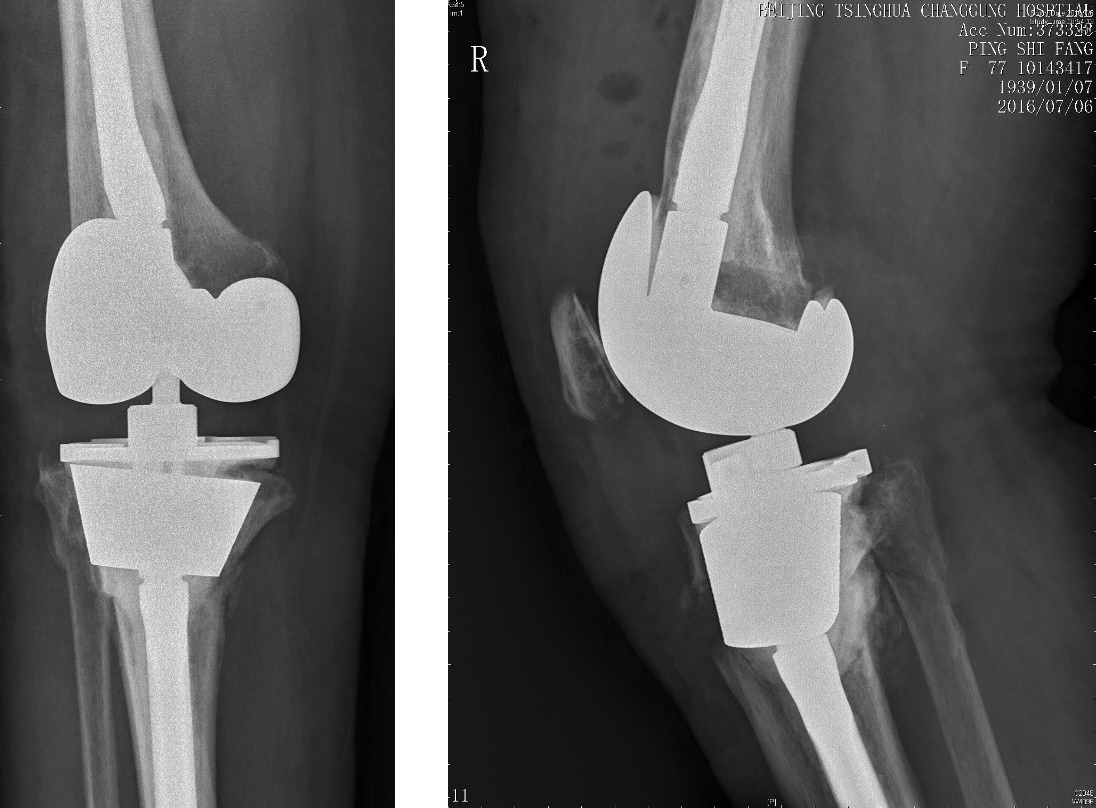

术前平片——显示为Felix IIB型 胫骨平台假体周围骨折

胫骨假体柄松动合并有严重的骨溶解、胫骨干骺端有腔洞样或节段性骨缺损